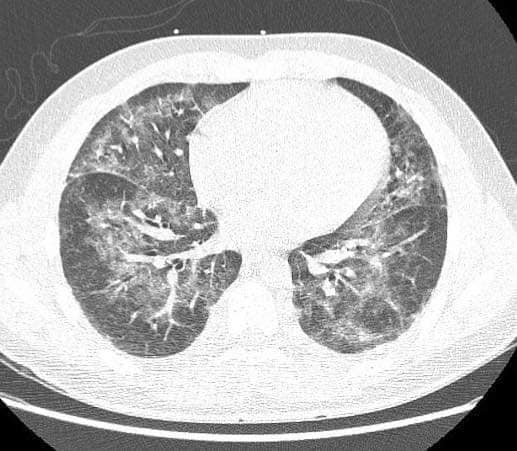

Evali, este boala asociată E-cigarette și produselor de vapat, medicii trag un semnal de alarmă pentru că afecțiunea poate fi fatală

„E-cigarette or Vaping Product Use-Associated Lung Injury (Evali) este o afecțiune medicală gravă în care plămânii unei persoane devin deteriorați din cauza substanțelor conținute în e-țigări și produse de vapare. Simptomele includ tuse, durere în piept, dificultăți de respirație, febră, greață, vărsături, diaree, dureri abdominale, pierdere în greutate și amețeli. Diagnosticul Evali este, în principal, un diagnostic de excludere a altor boli, iar tratamentul se bazează pe recomandările experților și depinde de gravitatea bolii. Majoritatea pacienților cu Evali se îmbunătățesc sub tratament cu doze mari de corticosteroizi sistemici. În plus, pacienții cu cazuri mai severe vor avea nevoie de spitalizare și, deoarece pot fi incapabili să respire singuri, pot necesita oxigen suplimentar sau ventilație mecanică”, subliniază prof. dr. Traian Mihăescu, medic primar pneumolog.

„Principalul factor de risc pentru dezvoltarea Evali este utilizarea curentă sau anterioară a unui dispozitiv de vaping, în special a celor care conțin THC (Tetrahydrocannabinol). Potrivit Centrelor de Control al Bolilor din SUA, peste 80 la sută dintre persoanele spitalizate din cauza Evali au raportat utilizarea de produse de vaping care conțin THC, deși mulți au declarat, de asemenea, că au folosit produse care conțin nicotină”, susține prof. dr. Traian Mihăescu.

Bolile generate de utilizarea țigărilor electronice sunt definite, în prezent, cu termenul de Evali, din limba engleză, care înseamnă boală pulmonară legată de utilizarea țigărilor electronice

„Alți factori de risc pentru Evali includ vârsta sub 30 de ani, identificarea ca grup rasial, etnic, altul decât cel alb, și utilizarea de produse contrafăcute care conțin THC, comercializate sub denumirea Dank Vapes. Pacienții cu afecțiuni medicale cronice, inclusiv boli cardiace, boli pulmonare cronice și diabet, precum și creșterea vârstei ar putea prezenta un risc mai mare de morbiditate și mortalitate mai mare în rândul unor pacienți Evali”, adaugă prof. dr. Traian Mihăescu în legătură cu boala care face ravagii în rândul tinerilor.